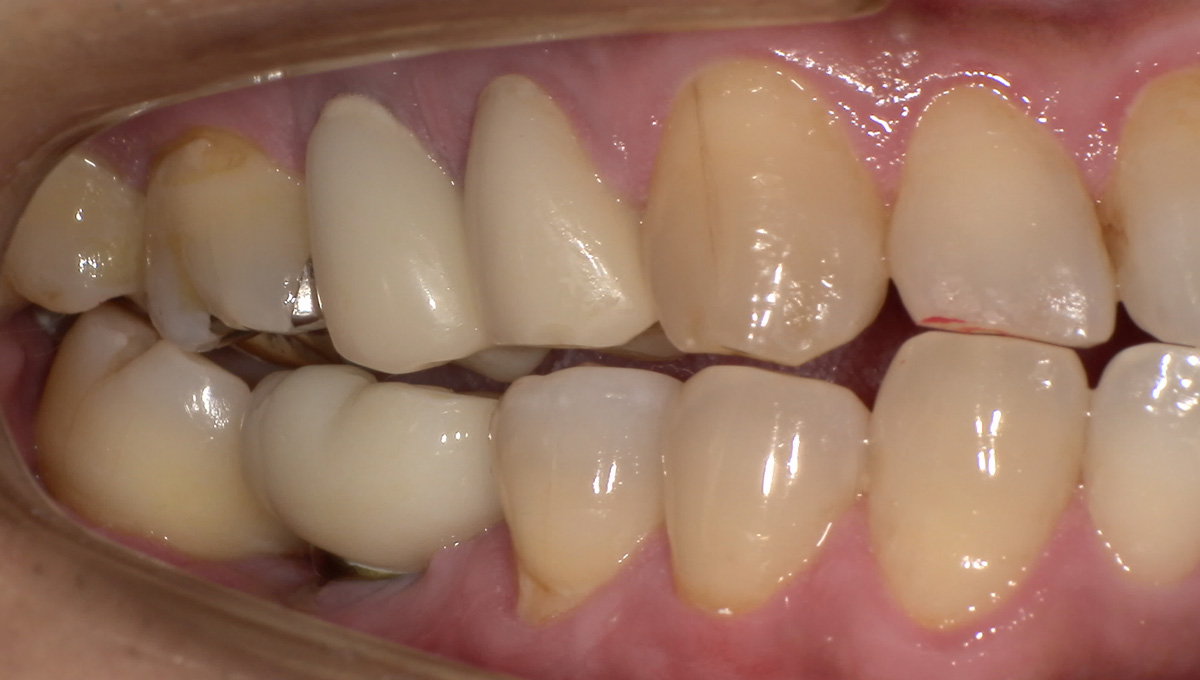

仮歯の調整期間を経て、セラミックの歯が入りました。

レントゲン画像 治療前 インプラント治療後